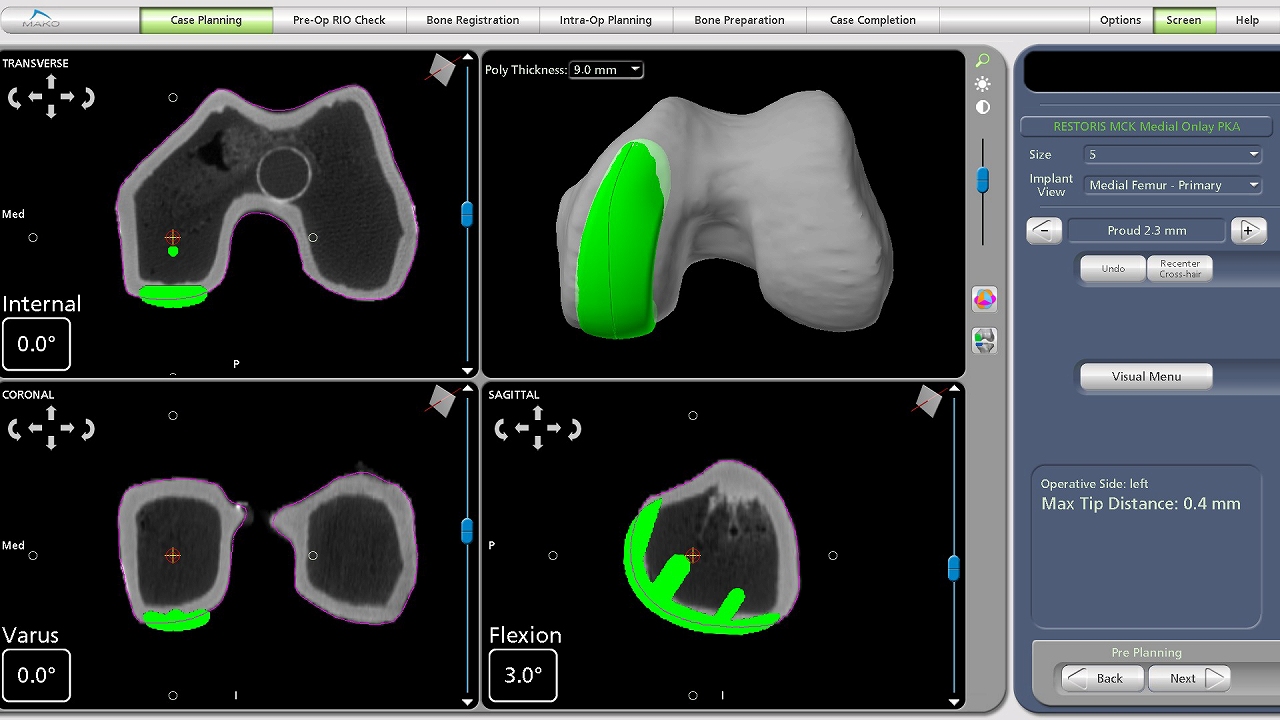

Makoシステム画像:UKA(単顆置換術)

手術支援システム「Mako」

当院は令和7年6月に愛知県内では6台目、東三河地域では初の導入となる、ロボティックアームを用いた人工股関節・膝関節の手術支援システム「Mako」(読み方:メイコー)(日本ストライカー株式会社)を導入しました。これにより、蒲郡市民病院整形外科の人工股関節・膝関節全置換術において、より低侵襲な手術の提供が可能になりました。

Makoシステム画像:TKA(全置換術)

Makoシステムのロボティックアームは、術中に医師が操作して動かし、人工関節を設置する際に傷んだ骨を削るために使用します。ロボティックアームは、人の手のようにぶれることがなく、正確に動き、止まります。その為、三次元CTデータをもとに事前に作成した治療計画から外れることなく、治療計画通り、正確な骨切りが可能になり、血管・神経の損傷を最小限に留めることが期待できます。

緑色のエリアが事前に計画した削られる部分です。医師が計画通り削ると色が白に変わります。 医師は、モニターに映し出された3D画像でリアルタイムに確認します。 予定外のエリアに刃やドリルが動くことをロボティックアームが制御するため、予定外のエリアが削られる心配がありません。

画像提供:日本ストライカー株式会社